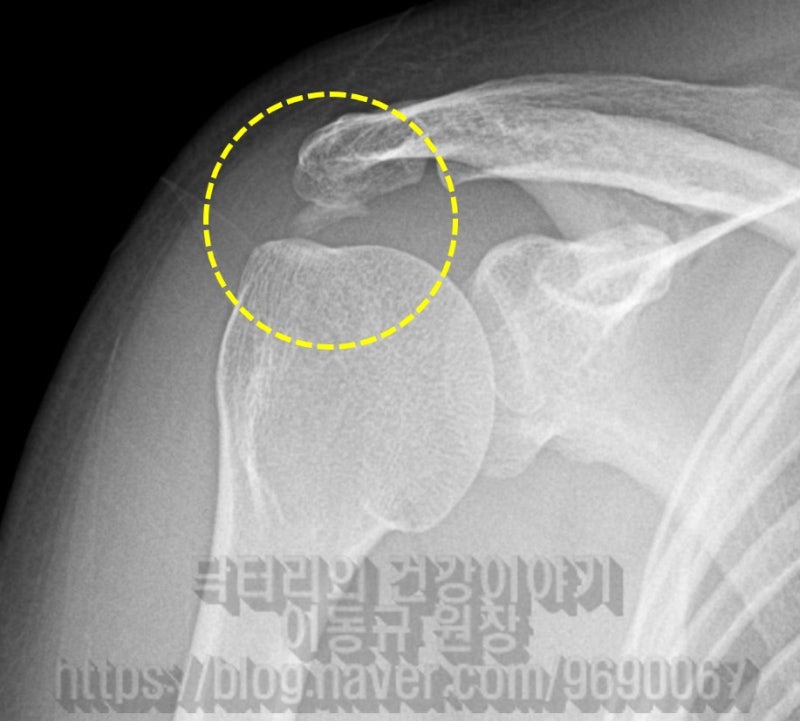

X-ray 사진을 보면 노난 원안에 극상근 부위의 석회성 건염이 보입니다. 빨간 점선으로 표시된 것이 석회입니다.